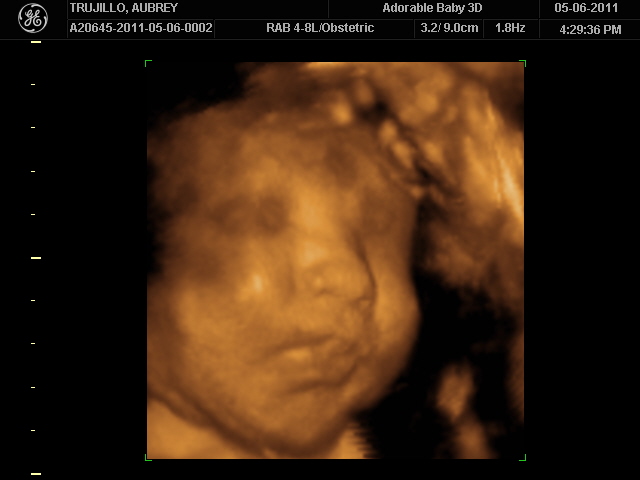

Baby looks like Matthew, I think... but it could just be the bald head that's making me think that!  It was moving around a lot and I swear it waved at us :)12 weeks

20 weeks - profile20 weeks - Profile again20 weeks - Right foot!20 weeks - sucking thumb!!!!20 weeks - hand near face20 weeks - flexing his bony arms!20 weeks - hiding from mommy and daddy!20 weeks - it's a boy!33 weeks - 3D!33 weeks - 3D!33 weeks - 3D!